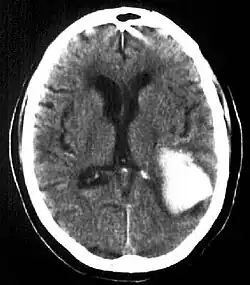

| Multiple intraparenchymal hemorrhage | |

Intraparenchymal hemorrhage is one form of intracerebral bleeding in which there is bleeding within brain parenchyma. The other form is intraventricular hemorrhage).[1]